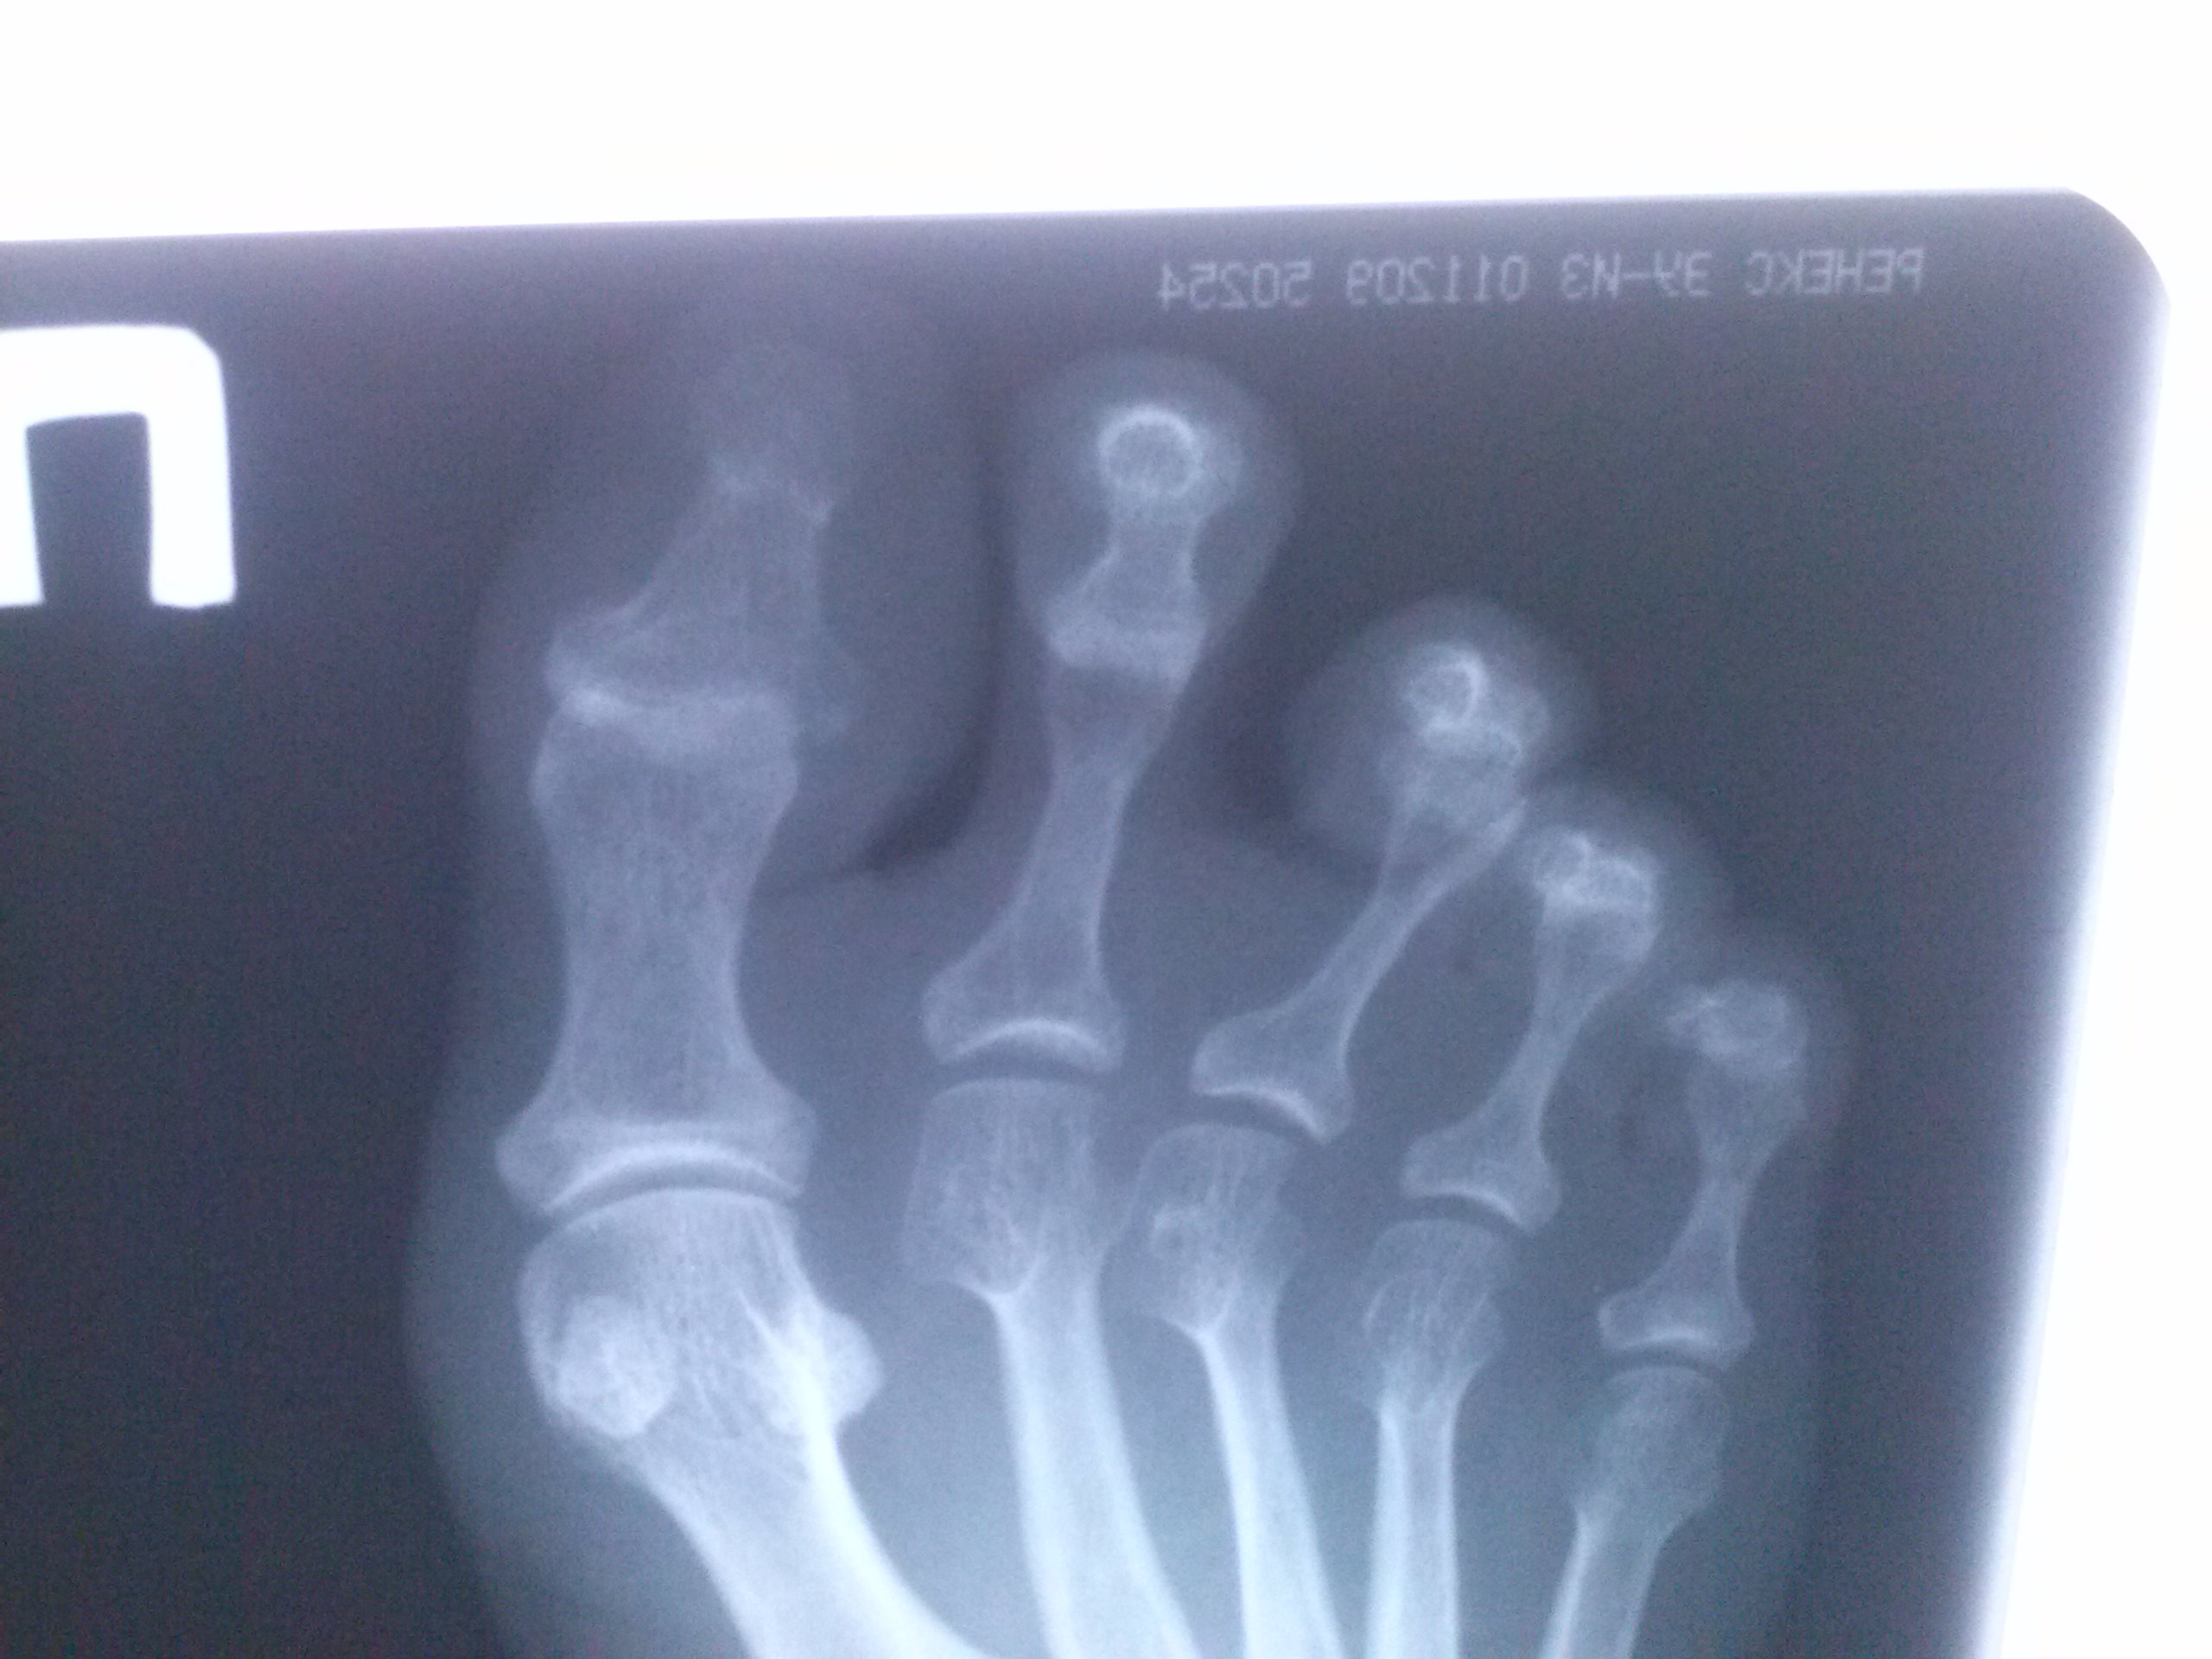

Мужчина, 55 лет. Палец болит уже неск месяцев - терпит. В направлении подагра, но как-будто не слишком похоже на нее. Непонятным для меня выглядит прерывистость костной плотности. Подскажите,...

Тип: Клиническое наблюдение

Область: Скелетно-мышечная система

Модальность: Rg

Дата: 03.10.2018 - 11:38